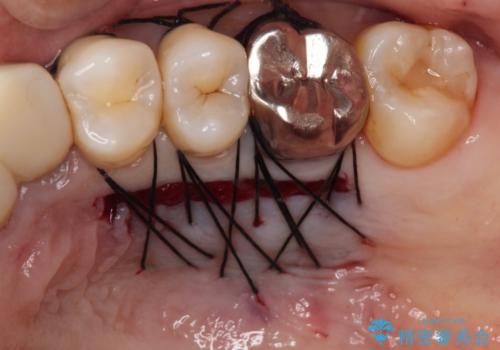

歯肉が痩せてしまっている状態を改善するため、口蓋から歯肉の結合組織を採取し、移植することで厚みを増大させることとし、その後オールセラミックブリッジにて補綴治療を行うこととしました。

1回の歯肉移植により歯肉の厚みは大幅に改善されましたが、折角なのでもう少し大きくしたいとの要望があり、2回目の処置も行うこととしました。

厚みも高さも十分な歯肉量を獲得することができました。